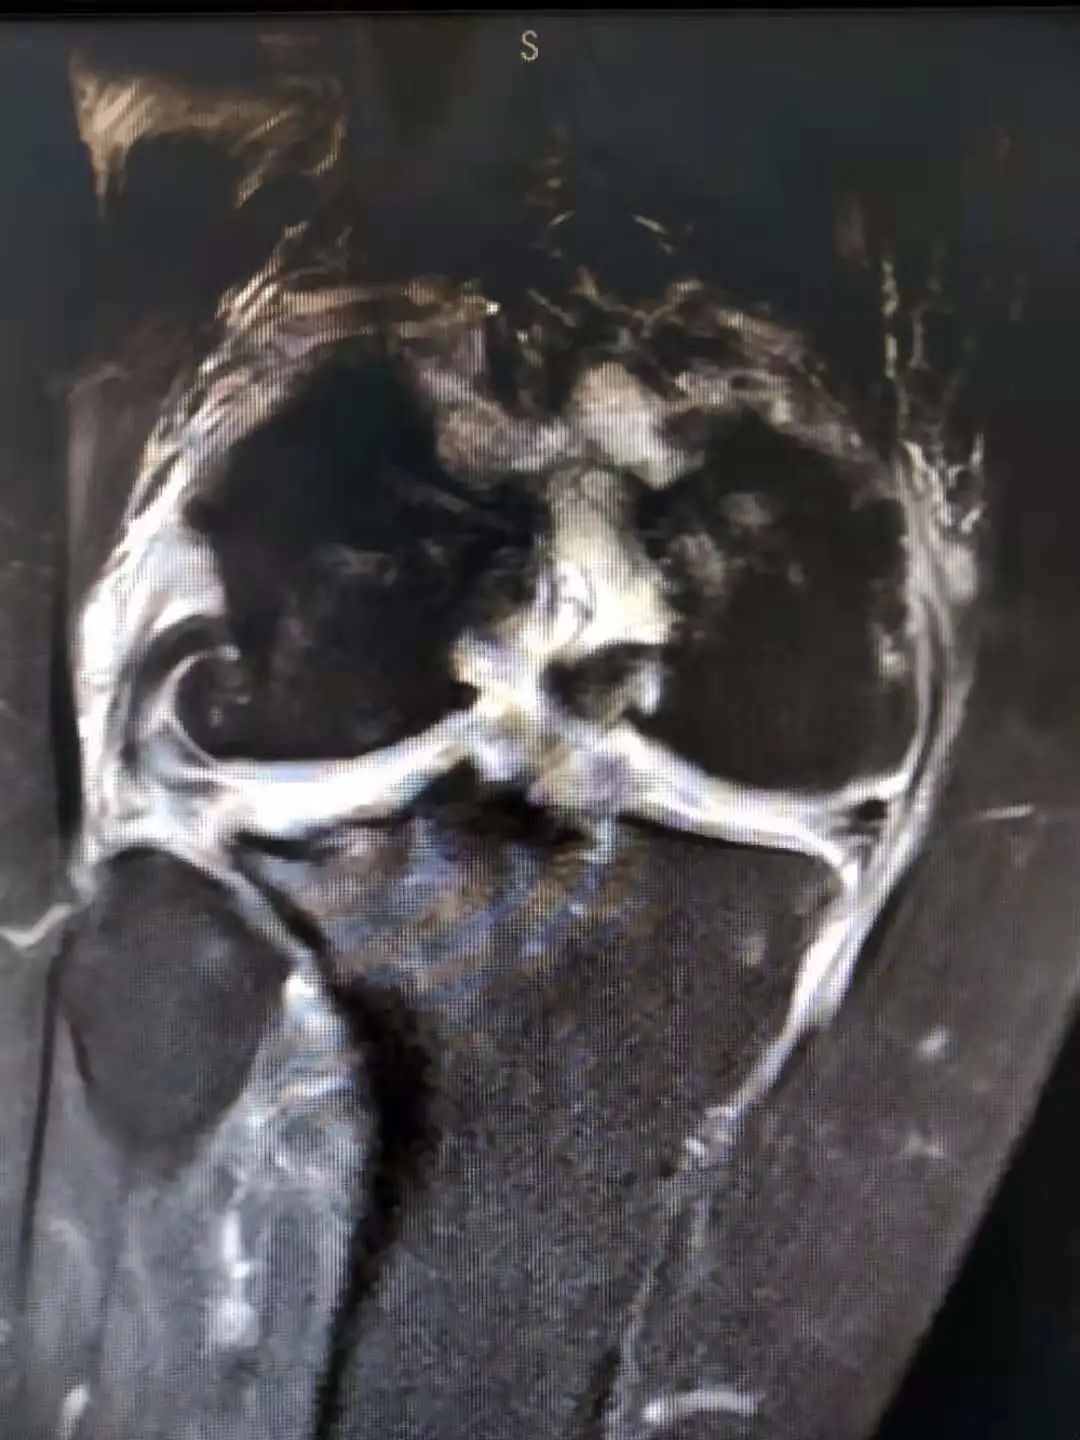

小镜子解决大问题——人民医院骨科开展关节镜微创手术获赞!

硬核设备上新丨高清极速成像,省内首台全数字3.0T磁共振落户招远市人民医院